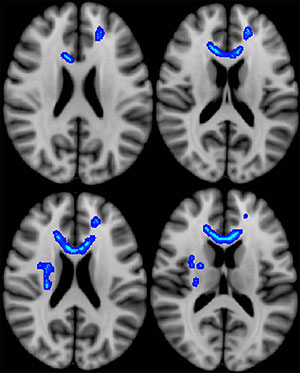

Differences in white matter microstructure may partially account for the variance in functional outcomes among veterans who sustained combat-related mild traumatic brain injury (TBI), according to new research.

Overall, veterans had a mean of 46 health care visits per year during the follow-up period. Cumulative health care visits over time were inversely correlated with diffusion anisotropy of the splenium of the corpus callosum and adjacent parietal white matter. Clinical measures obtained during initial postdeployment evaluation were not predictive of later functional status.